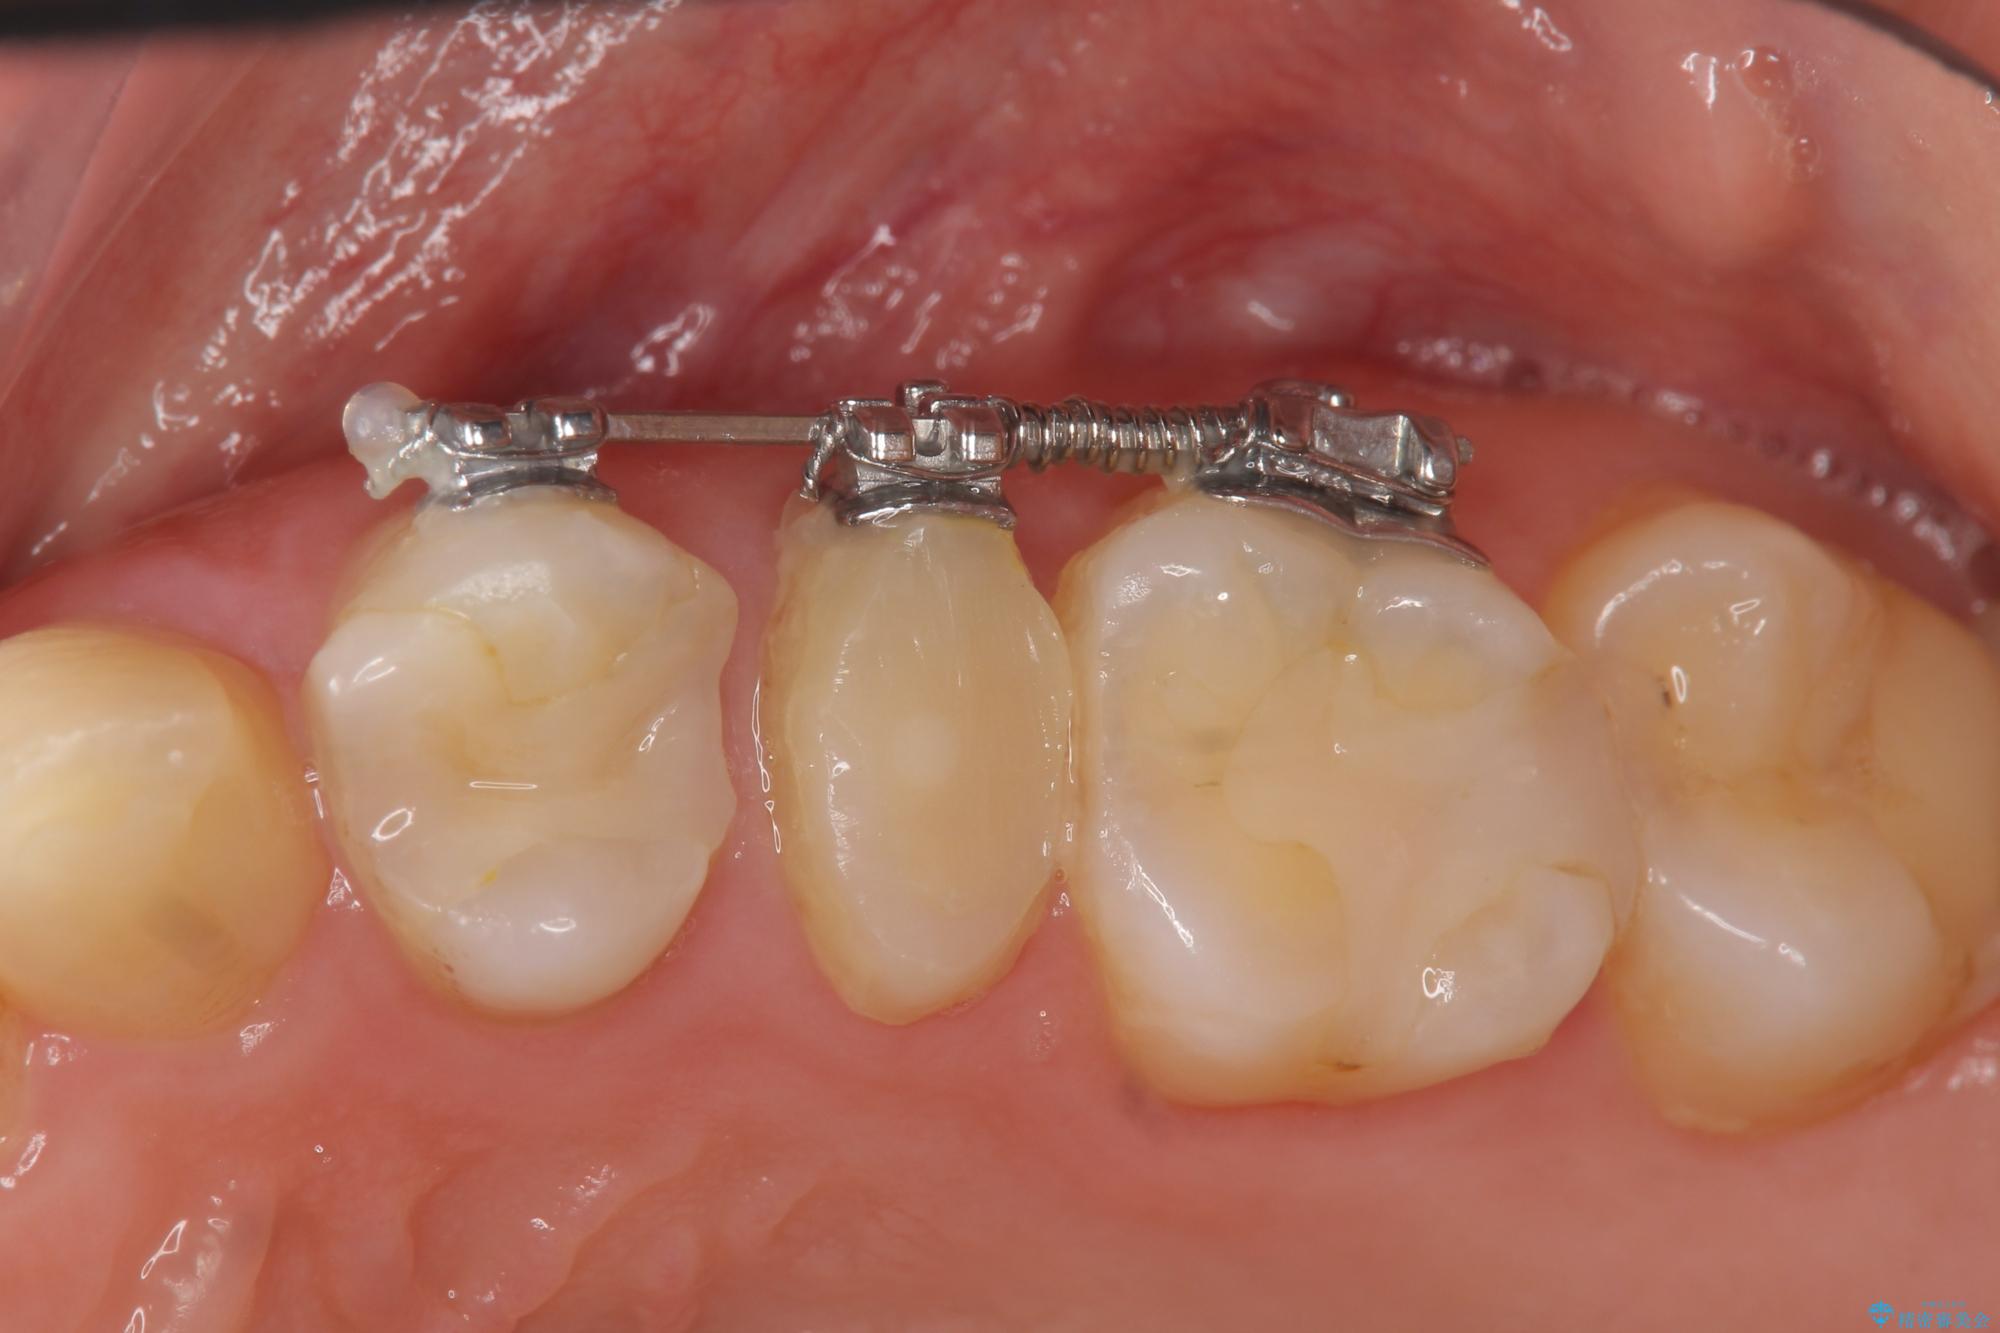

- 部分ワイヤー矯正

当初、歯ぐきよりも深い虫歯のぞんざいや、歯のポジションに問題がありましたがマルチブラケットを用いた部分矯正を行うことで適切な位置へと歯を移動させ、歯周環境を整えたセラミック治療を行うことができました。